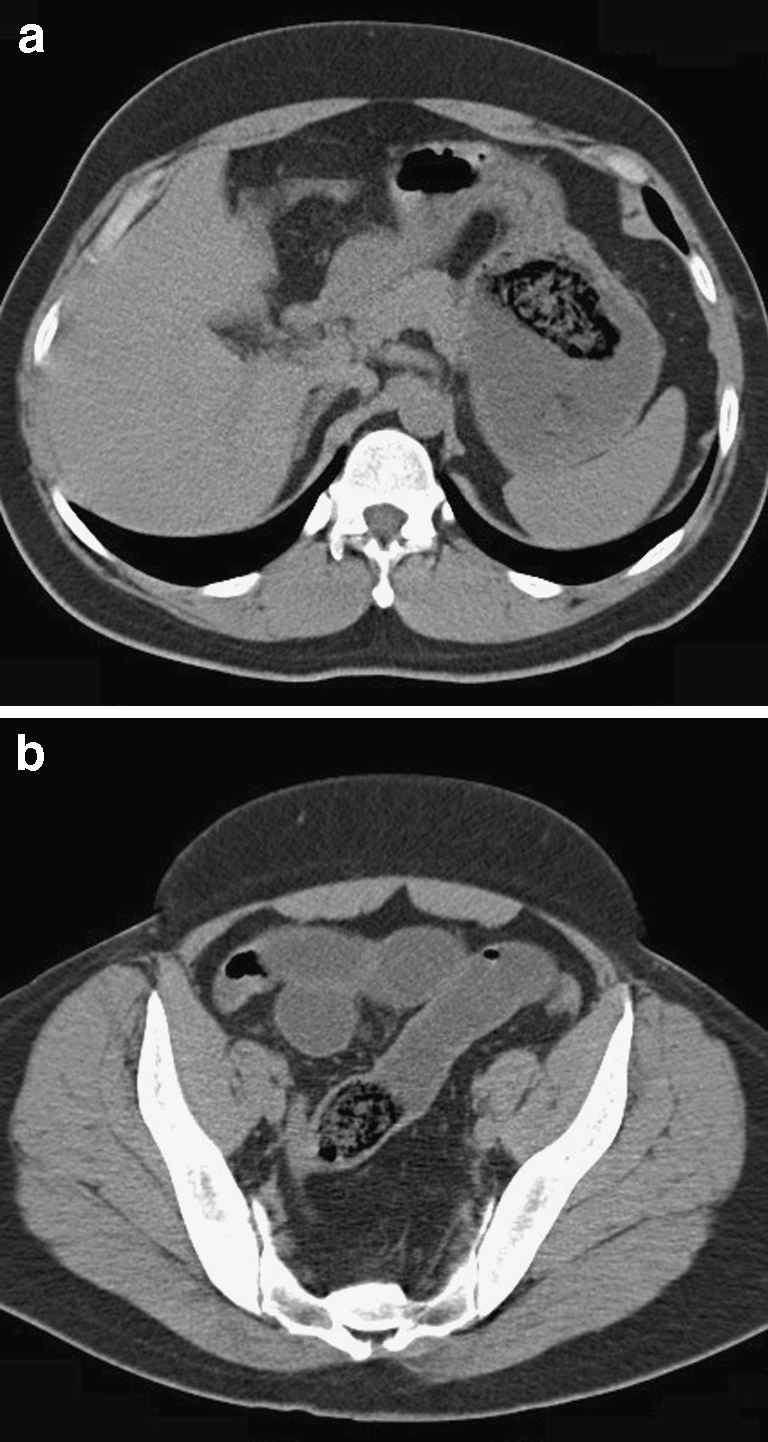

Fig. 2.

CT scan of the abdomen showing one foreign body in the stomach (a) and one in the dilated duodenum (b)